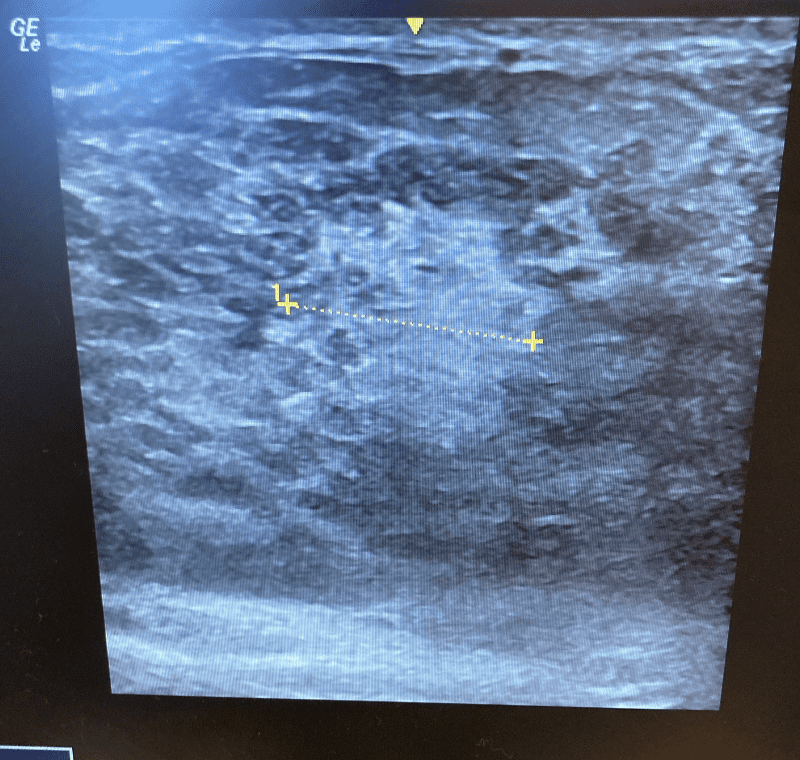

When you massage an early “plug” you can develop a phlegmon (mass-like area with broken capillaries and inflammatory fluid). If massage and pumping or overfeeding continues, the phlegmon coalesces into an abscess.

Think of the progression like this:

#1: Normal grapes

#2: Grapes that got smashed in your grocery bag. It is a mix of skin, grape pulp, and liquid. This is a PHLEGMON.

#3: If you were to continue smashing these grapes and adding more grapes to the mix, you would get more and more liquid and less solid material. This is an ABSCESS.